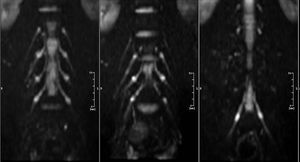

Diffusion-Weighted MR Neurography in a healthy volunteer

DWI provides great image contrast between the peripheral nerves and the adjacent tissue such as vessels and muscles.